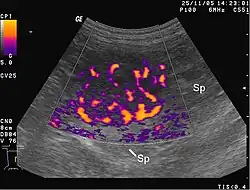

Darstellung der verstärkten Vaskularisation einer Milzmetastase beim Hund sonografisch per amplitudenkodiertem Doppler. Der Tumor ist gekennzeichnet durch die Farbansammlung im Zentrum des Bildes. Sp-Milzgewebe